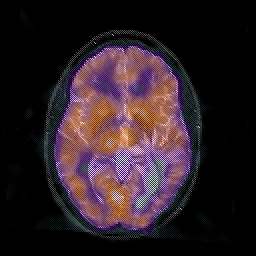

Glioblastoma multiforme overlay -- Slice #27

[Home][Help][Clinical][Tour 1][Tour 2][Tour 3] Slice 27